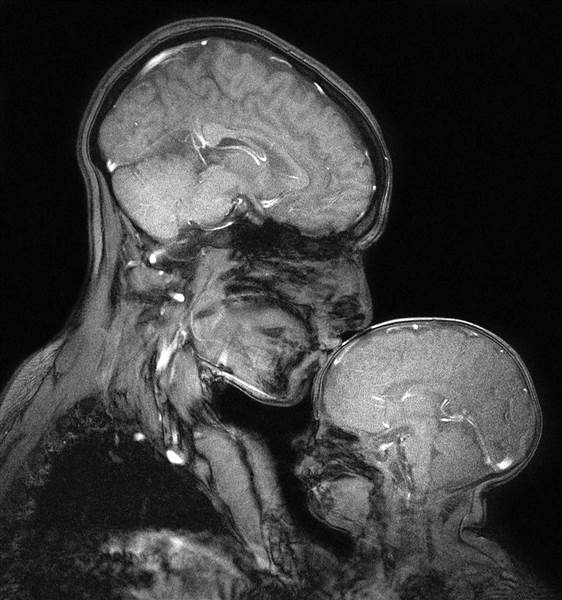

Сложности проведения МРТ головы детям

В некоторых случаях назначается МРТ головного мозга плода. Обычно это требуется в тех ситуациях, когда есть риск развития врождённых заболеваний. Специалисты способны сегодня достаточно точно определять состояние мозга в целом и различных сосудов в отдельности. Этот метод позволяет выявить степень повреждения тканей, а вместе с тем и развитие болезни в целом.

Лучше всего для исследований сосудов головного мозга у детей с помощью МРТ выбирать современные модели аппаратов. Напряжение магнитного поля 1,5 Тл позволяет получить наиболее чёткие изображения головного мозга. Благодаря этому врачи сразу видят даже мелкие родовые травмы, пороки развития и другие отклонения в работе мозга. На компьютерной модели сразу проявляются опухоли и повреждения структуры кровеносной системы.